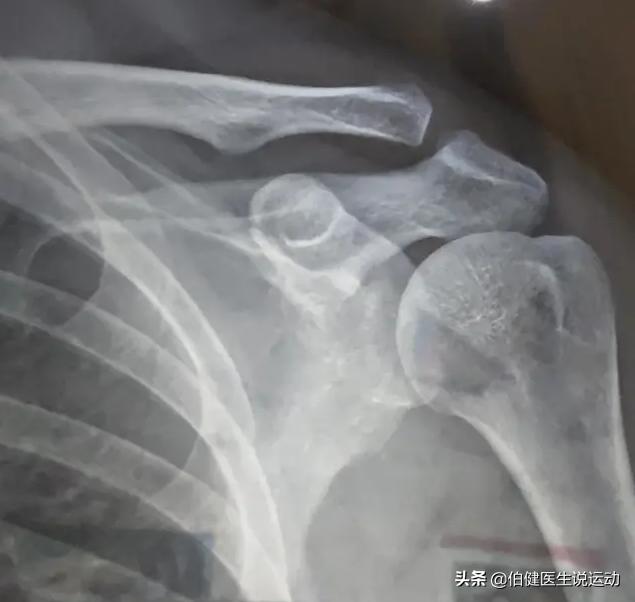

肩锁关节脱位Rockwood分型

肩锁关节脱位Ⅰ型、Ⅱ型影像学上不明显。容易被忽略。这就需要照特殊的X线照片明确诊断了:

1、让患者两手分别提重物约2.5kg,同时摄双侧肩锁关节正位片进行对比,常可发现患侧锁骨外端与肩峰间距离较健侧增大,全脱位者X线照片,可发现锁骨外侧端与肩端完全分离,向上移位较明显。

2、射线向上成角10°~15°位拍摄X片可更明确肩峰与锁骨远端间距离。